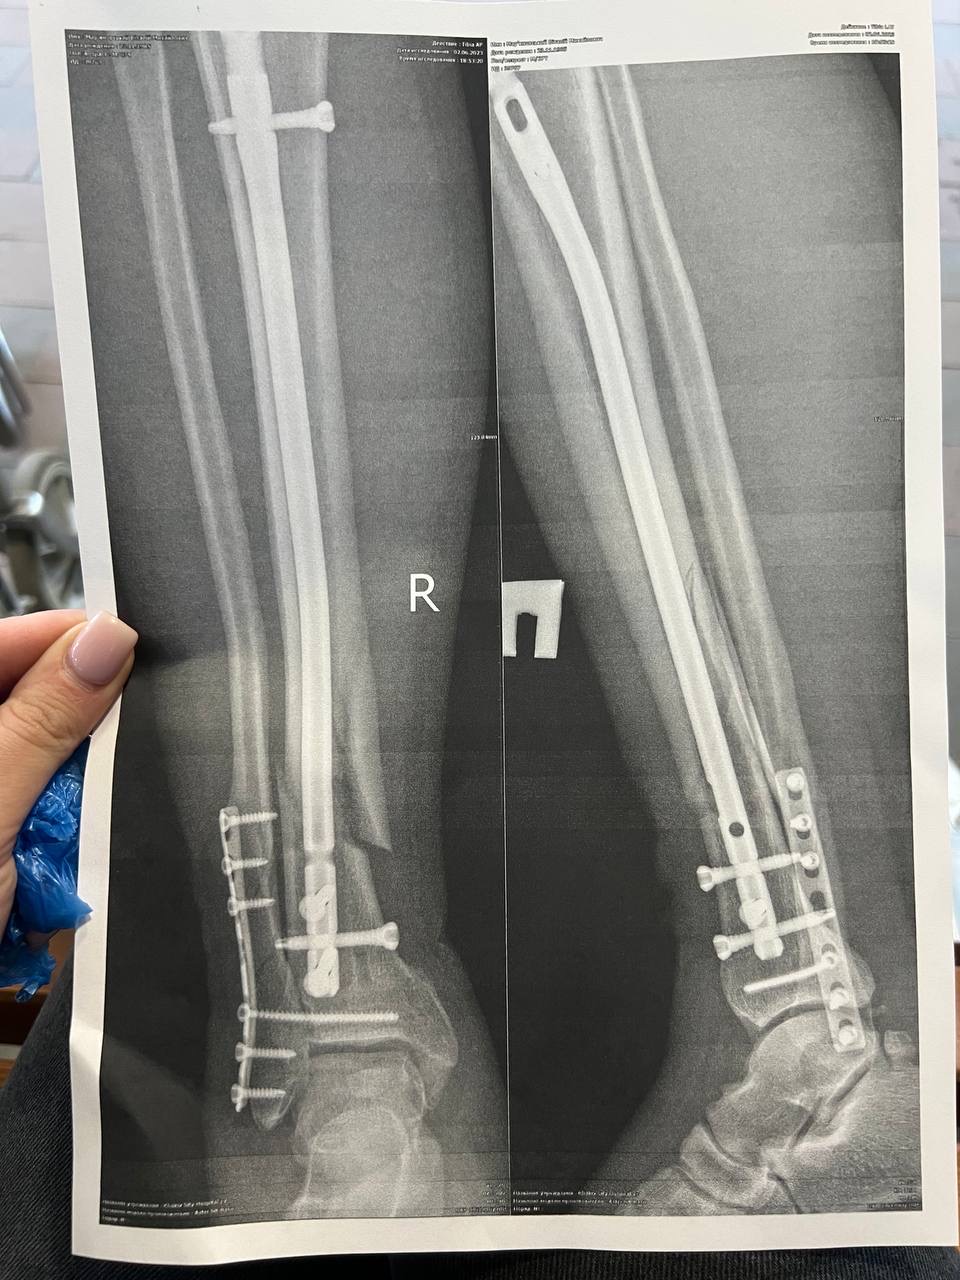

Гравець команди МЖК Віталій Мар'яновський отримав важку травму

Команда МЖК відповідально поставилася до підвищення у 5 лігу, тож збільшила інтенсивність тренувань. На жаль, саме на тренуванні перед початку турніру Віталій отримав важку травму - перелом ноги зі зміщенням та великою кількістю уламків.

Номер картки для допомоги: 4149 6293 5404 1089 (дружина Віталія)